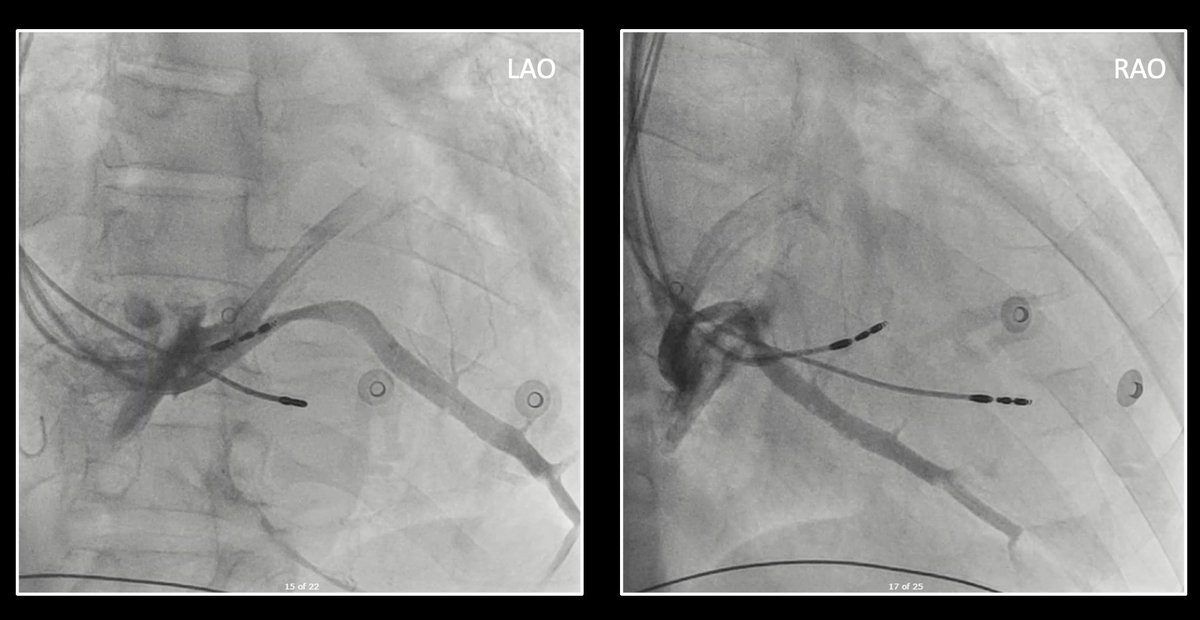

1/ I wonder what #Epeeps would do for a 62yo male patient with NICMP, LBBB QRSd >200ms, LVIDd 71mm, LVEF12%? Conventional CRT, LBB-CRT, LOT-CRT, too advanced for CRT? For CRT, any vendor preferences? @finnakerstrom @James_Elliott01 @enes_elvin @riley_guntrip @chris_monkhouse

7/ Slow pathway targeted for ablation. 6s of RF was enough to totally remove the two for one responses (TFORs). Post ablation everything normalised. I thought this was a rare but satisfying case. @finnakerstrom